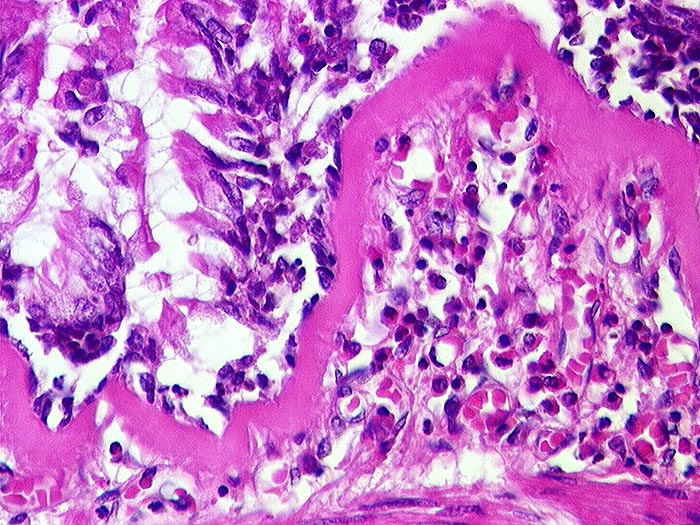

AP/ Asthma bronchiale

Asthma bronchiale

Bronchus

Morphologie

Pathologischer Befund